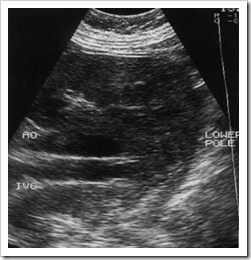

In the horseshoe kidney, the kidneys lie one on each side of the abdomen but their lower poles are fused by a connecting band of renal tissue, or isthmus, which lies anterior to the aorta and IVC (Fig.below). The kidneys tend to be rotated and lie with their lower poles medially. It may be difficult to visualize the isthmus due to bowel gas anterior to it but a horseshoe kidney should always be suspected when the operator is unable to identify the lower poles of the kidneys confidently. When the isthmus can be seen, it is important not to confuse it with other abdominal masses, such as lymphadenopathy. CT is occasionally performed because of this but normally clarifies the findings.

Ultrasound images of Coronal section through a horseshoe kidney with the isthmus of the kidney anterior to the aorta and IVC.